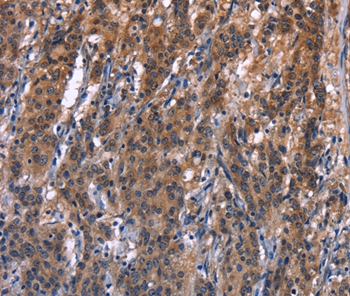

Immunohistochemical analysis of paraffin-embedded Human thyroid cancer tissue using #37592 at dilution 1/40.

Immunohistochemical analysis of paraffin-embedded Human gastric cancer tissue using #37592 at dilution 1/40.